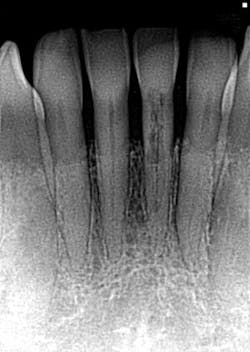

- This is another case of what could easily be misdiagnosed as internal resorption on tooth #No. 24. If you look closely in Figure 7, the outline of the canal can be seen.

- In Figure 8, the lesion is advanced significantly (one-and-a-half years had gone by) the irregular borders and moth-eaten appearance is easily observed.

- Definitive diagnosis: external resorption.